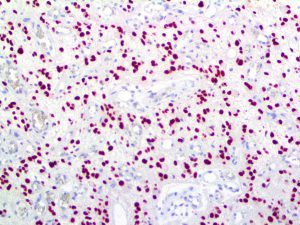

It is the ICU physician who is most likely to witness one of the deadliest manifestations of the abnormal immunological response, the cytokine storm syndrome (CSS). This response is also referred to by some as the cytokine release syndrome (CRS). CSS is characterized by continuous activation and expansion of macrophage and lymphocyte populations, which secrete large amounts of cytokines, causing the cytokine storm. This massive cytokine release is akin to hemophagocytic lymphohistiocytosis (HLH) disease, a syndrome characterized by initial unchecked and persistent activation of cytotoxic T lymphocytes and NK cells.

Clinical and laboratory manifestations of HLH include fever, enlarged liver and/or spleen, neurologic dysfunction, coagulopathy, liver dysfunction, cytopenias (i.e., low levels of erythrocytes, leukocytes, and/or platelets), hypertriglyceridemia, hyperferritinemia, hemophagocytosis, and eventually diminished NK cell activity as the immune system becomes progressively paralyzed. HLH can be familial (primary HLH) or secondary to another disease process (sHLH), such as rheumatic disease, in which it is referred to as macrophage activation syndrome (MAS, characterized by elevated ferritin).